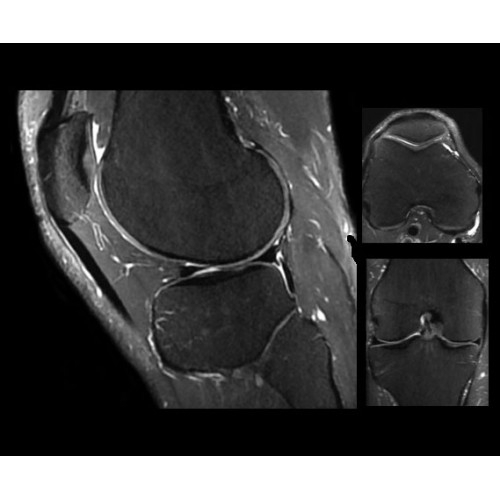

Система SIGNA PET/MR предлагает впечатляющие клинические возможности и открывает доступ к наиболее полным пакетам программных приложений.

• TurboTOF — инновационная технология позволяет корректировать коэффициент затухания сигнала и минимизировать потери анатомических данных, создавая МР-систему для количественной визуализации.

• Q.Clear — в основу технологии легли накопленные знания о том, как минимизировать помехи при реконструкции и получить четкое изображение. При значительном улучшении качества изображения сохраняется точность расчетов. Сочетание технологии TOF и реконструкции Q.Clear — ваш надежный помощник для получения точных и достоверных данных.

• Приложения для коррекции артефактов движения — используйте наиболее широкий набор инструментов, таких как PROPELLER, PROMO и навигаторы Pencil Beam, позволяющих снизить влияние непроизвольных или физиологических движений на качество изображений.

Стандартный пакет приложений SIGNA Works позволит вам достичь желаемых результатов в клинической практике благодаря набору высокоэффективных средств визуализации. Программные приложения, входящие в состав данных клинических пакетов, включают широкий спектр контрастов, функции обработки 2D- и 3D-данных, а также возможность коррекции артефактов движения. SIGNA Works предоставляет набор инструментов, необходимых для проведения эффективного клинического исследования.